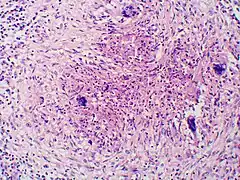

Tissue biopsy of skin or other organs may be required in order to diagnose extra-pulmonary disease. Blastomycosis is histologically associated with granulomatous nodules. Commercially available urine antigen testing appears to be quite sensitive in suggesting the diagnosis in cases where the organism is not readily detected. While culture of the organism remains the definitive diagnostic standard, its slow growing nature can lead to delays in treatment of up to several weeks. However, sometimes blood and sputum cultures may not detect blastomycosis.[18][16][15]

Granuloma with early suppuration. Fungal organisms difficult to recognize at this low magnification. -

Large yeast-like fungi seen within giant cells at arrows. -

Large yeast-like fungi seen within giant cells at arrows.Budding yeasts in cytoplasm of giant cells at arrows. Broad-based budding and double contoured cell wall seen in the giant cell in the center is characteristic of Blastomyces dermatitidis.